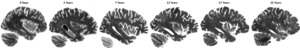

As the process of fixation with formalin significantly impacts T1 relaxation times and consequently the gray-to-white matter contrast of the tissue in T1 weighted (T1w) MRIs.5,7 Standard scans with Magnetization Prepared RApid Gradient Echo sequence (MPRAGE) were performed after a minimum of 4 months of fixation, to allow for the fixation process to complete for all brain regions, providing improved tissue contrast and signal to noise ratio (SNR). To verify the impact of fixation on different MRI contrasts, a subset of the specimens (N = 10) was also longitudinally scanned, from 0 to 120 days of fixation with 10% formalin. Figure 2 shows the impact of fixation on co-registered T1w MRIs of a DBCBB brain specimen that was scanned longitudinally from 0 days to four months of fixation. Note the changes in gray matter to white matter tissue contrast, noticeable at 3 days of fixation in the cerebellar and deep gray matter regions, expanding to the occipital lobe, and stabilizing in all brain regions after 90-120 days of fixation.